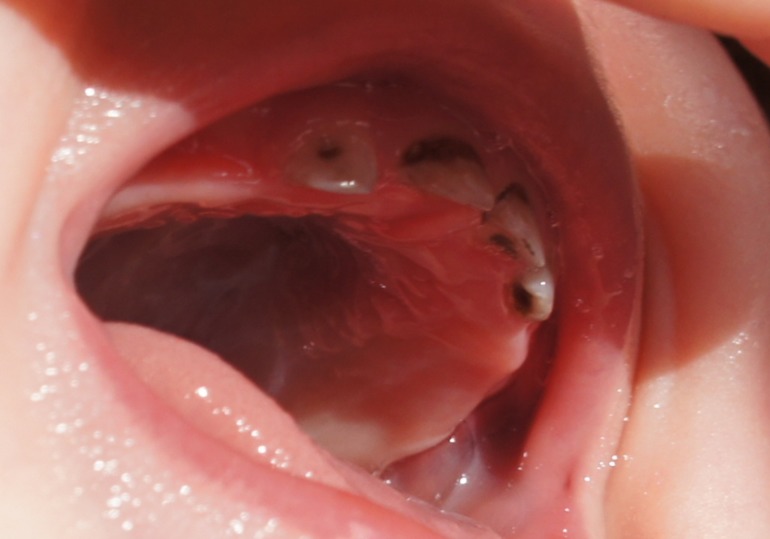

Мы сфотографировали наши посеребренные зубики.

Сразу они не почернели, а через два дня стали такими:

Мы обеспокоены тем, что, возможно, посеребрили нам поздно, и процедура больше навредит, чем принесет пользы. Так ли это, и в целом, каково состояние зубиков на Ваш взгляд?

Здравствуйте.Вы правы- посеребрили Вам уже поздно.Такие зубы необходимо лечить,т.к. серебрение в таком случае не останавливает процесса.